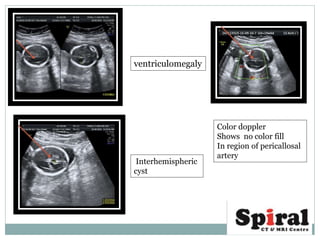

 colour Doppler study may show an abnormal course of pericallosal arteries

ventriculomegaly

Interhemispheric

cyst

Color doppler

Shows no color fill

In region of pericallosal

artery